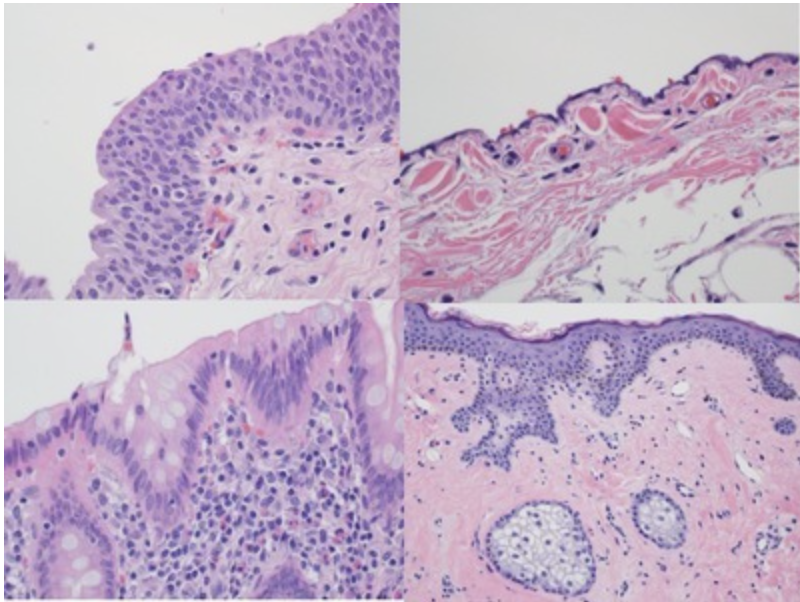

In this image, identify the columnar epithelium.

The shapes and dimensions of epithelial cells are quite variable, ranging from columnar, cuboidal to low squamous cells. In this image, the columnar epithelium is characterized by the cells being taller than they are wide, and the nuclei are basally located.

In this image, identify the structure that brings nutrients and oxygen to both the epithelial and connective tissues!

Most epithelia rest on connective tissue that contains the microvasculature bringing nutrients and oxygen to both tissues. Notice the red blood cells within these vessels.

In this image, identify the lamina propria!

The conective tissue that underlies the epithelia lining the organs of the digestive, respiratory and urinary systems is called lamina propria

In this image, identify the structure that forms a scaffold for epithelial repair and regeneration!

Basement membranes have many functions. They provide structual support and polarity to epithelial cells and attach epithelia to underlying connective tissue. Proteins of the layered meshwork help filter substances entering the epithelium from below; concentrate mitogenic growth factors, and form a scaffold for epithelial repair and regeneration.

This epithelium is an example of a …

The correct is answer is “Squamous Epithelium”. Very thin cells that line body surface. This is a case of mesothelial cells that line internal organs. This epithelium facilitates movement of the viscera.

The correct answer is “columnar epithelium”. Cells are taller than wide. Nuclei are basally located. This picture is from the epithelium of an appendix. It provides protection and secretion.

This represents an example of a …

The correct answer is a “Stratitified” epithelium, or more precisely a stratified squamous epithelium from the skin. The cells form multiple layers with the less differentiated ones near the underlying connective tissue. The main functions of this squamous epithelium are protection and prevention of water loss.

Identify the epithelium with one of its functions being distensibility.

The correct answer is “Transitional epithelium” that lines the bladder. This epithelium lines much of the urinary tract, extending from the kidney pelvis to the proximal part of the urethra. These cells are specialized to protect underlying tissues from the hypertonic and potentially cytoxic effects of the urine. Unique morphological features of the cells allow distension of the transitional epithelium as the bladder fills. The picture of the tansitional epithelium in the question derives from an empty bladder. The same epithelium looks as below when the bladder is full.